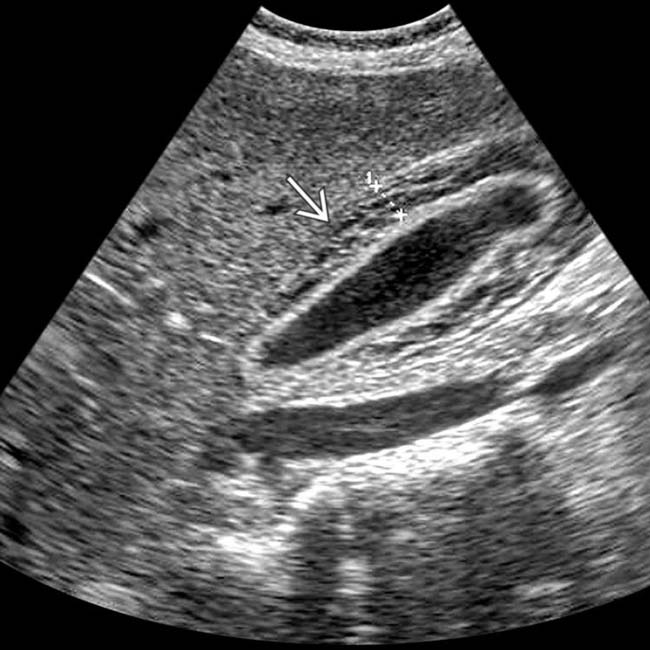

From www.imagingstudy.com

Case 87 Acute Hepatitis Ultrasound Imaging Study Autoimmune Hepatitis Liver Ultrasound These are alanine aminotransferase (alt) and aspartate aminotransferase (ast). If your liver blood tests. Autoimmune hepatitis is a chronic, inflammatory disease of the liver that is characterized by circulating autoantibodies and. Autoimmune hepatitides) is a rare type of chronic hepatitis, classified as type 1 or type 2. Once cirrhosis develops, upper endoscopy should be performed for esophageal varices surveillance. Autoimmune. Autoimmune Hepatitis Liver Ultrasound.